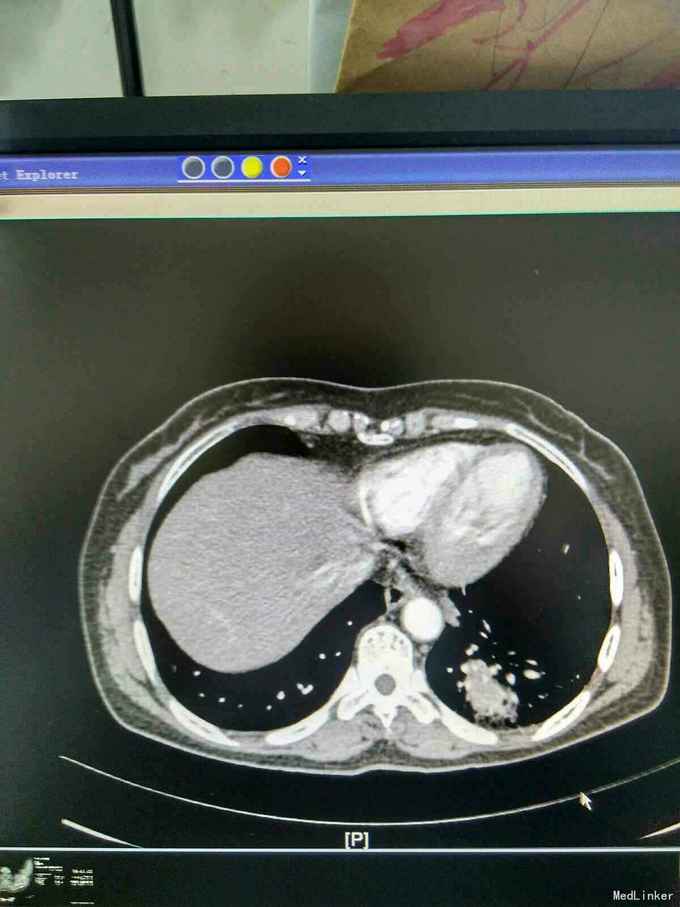

患者44岁女性,以“咳嗽咳痰间断咯血1月余”为主诉入院,入院前1月余不明显诱因出现咳嗽,呈阵发性非刺激性,咳黄白痰,每日五六口,间断咯血,色鲜红,每次10到50毫升不等,余无特殊不适,就诊当地医院摄胸部ct提示左下肺炎,予抗感染止咳化痰止血处理后症状反复,半月前复查胸部CT提示肺部阴影较前增大。

查体,神志清楚,浅表淋巴结未触及肿大,左下肺呼吸音减弱,可闻及少许湿性啰音。外院胸片示,左下肺斑片状实变阴影。

我院胸部ct增强,见左下肺病灶内见一异常供血血管,发自降主动脉,病灶周围见斑片状磨玻璃影。诊断为左肺下叶肺隔离症,转外科治疗。

患者外院胸部ct提示左下肺块影,原计划行ct引导下肺穿次活检术,我院胸部ct增强后发现,病灶为肺隔离症。遂转外科行左下肺切除术。